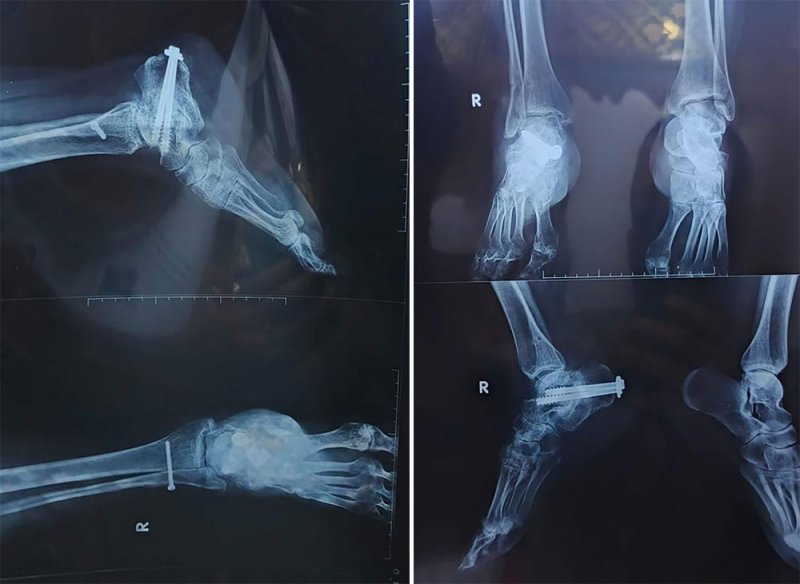

وتكمل نور “منذ ذلك التاريخ وأنا لم أنقطع عن زيارة المستشفيات، وأجريت 5 عمليات جراحية، لكن من دون جدوى بعدما تحوّلت حياتي إلى جحيم وبعد أن تبخرت 17 عامًا من عمري، جراء الربط البلاتيني في كاحلي، كما أنهكتنا المصاريف الكثيرة، وغلاء المراجعات الطبية والأدوية، في وقت لم أعد أملك شيئًا لبيعه لكي أتعالج بثمنه”.

ولا تزال السيدة العراقية مضطرة لزيارة المستشفيات الخاصة في كردستان العراق لإجراء فحوص دائمة لتأمين الأربطة البلاتينية في كاحلها، حالها حال نساء كثيرات تعرضن لبتر أطراف من أجسادهن بسبب تبعات الاحتلال والعمليات العسكرية في المدن المنكوبة.

وتقدر نسبة العجز في ساق نور بـ65 بالمائة، لهذا لا يحق لها الحصول على راتب الرعاية الاجتماعية، لأن القانون ينص على أن تكون نسبة العجز أكثر من 75بالمائة.